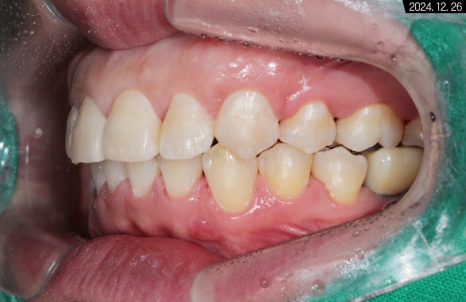

유지장치를 부착하고 난 후의 악궁 사진입니다.

수평 피개가 해소되었기 때문에

측면에서 봐도 중심선이 바릅니다.

둥글게 변하면서

교합 상태가 이상적인 모습을 보이네요.